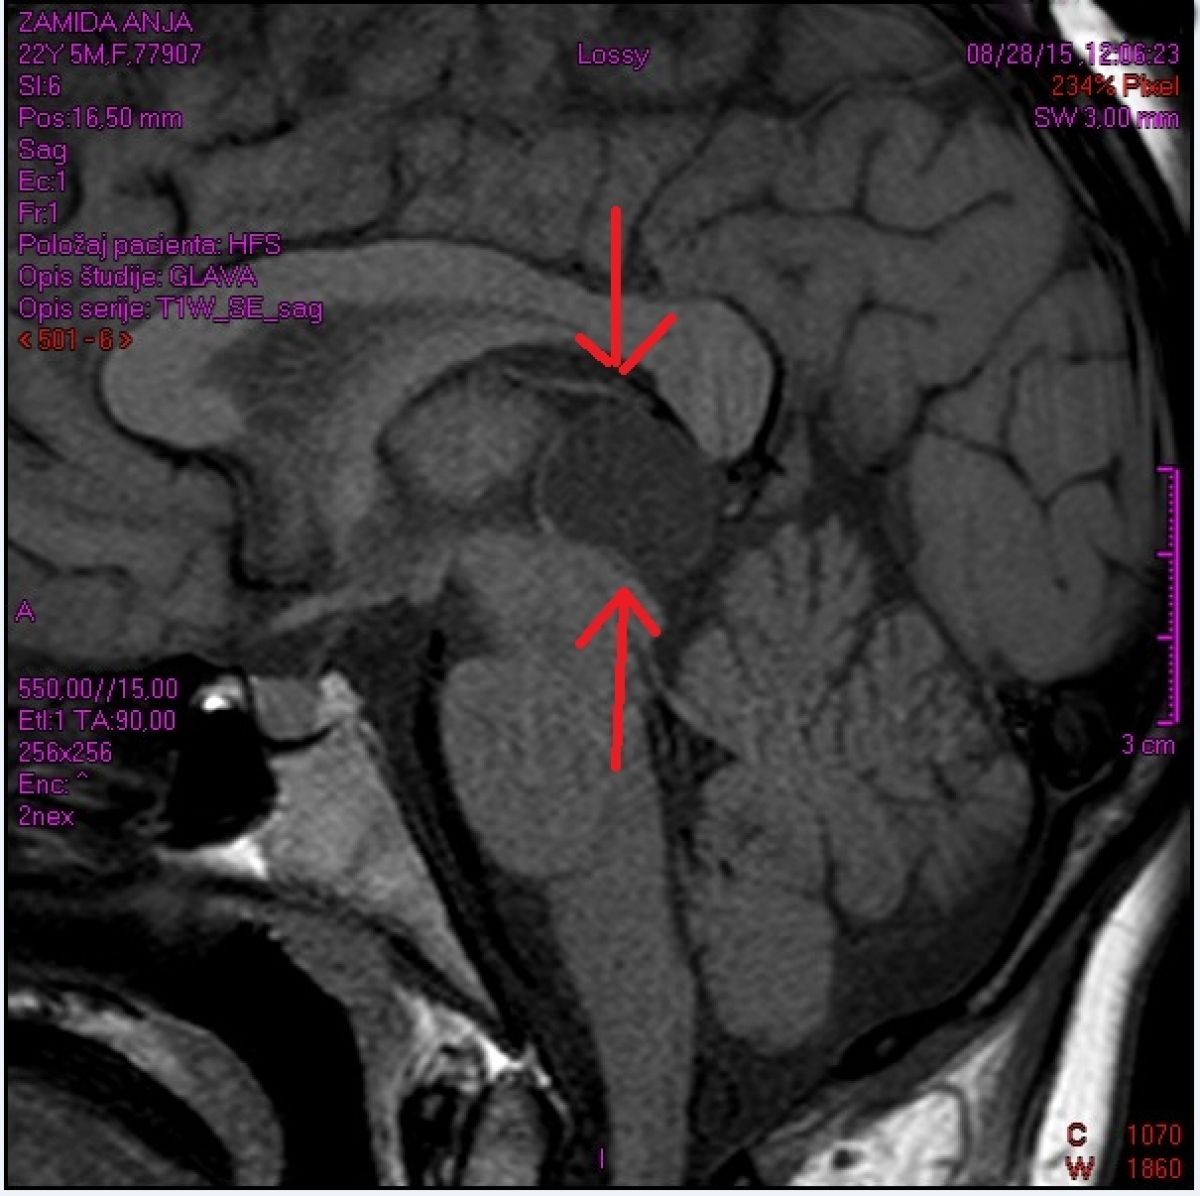

Cista pinealne žleze

Osebni Arhiv

Anjin posnetek z magnetne resonance je razkril šokantno resnico o nevarni cisti.

Ko je diagnozo ozavestila, se je odločila, da bo storila vse, kar lahko, da ji le ne bi odpirali glave. Hodila je k homeopatu, bioenergetiku, bioterapevtu, imelo je učinek, a kratkotrajne narave. Vrnile so se migrene, slab vid, bolečine v mišicah in kosteh. Dekle trpi za motnjami spanja, večinoma je lahko budna le nekaj ur, potem omaga in zaspi. Zbuja se s hudimi bolečinami v mišicah, z občutkom, da glava ni njena, a jo zelo boli. Pogled ima lahko usmerjen le naravnost, kakršnokoli drugačno premikanje oči dekle pahne v še večje bolečine. Z vsem tem mlado dekle živi vsak dan in sleherno noč. Cista pa raste, je pokazala zadnja magnetna resonanca, in treba jo bo operativno odstraniti. Zaradi rasti cista povečuje pritisk v lobanji in moti pretok likvorja (tekočine, ki obdaja možgane in hrbtenjačo). Simptomi zvišanega pritiska pa ogrožajo Anjine življenjske funkcije.